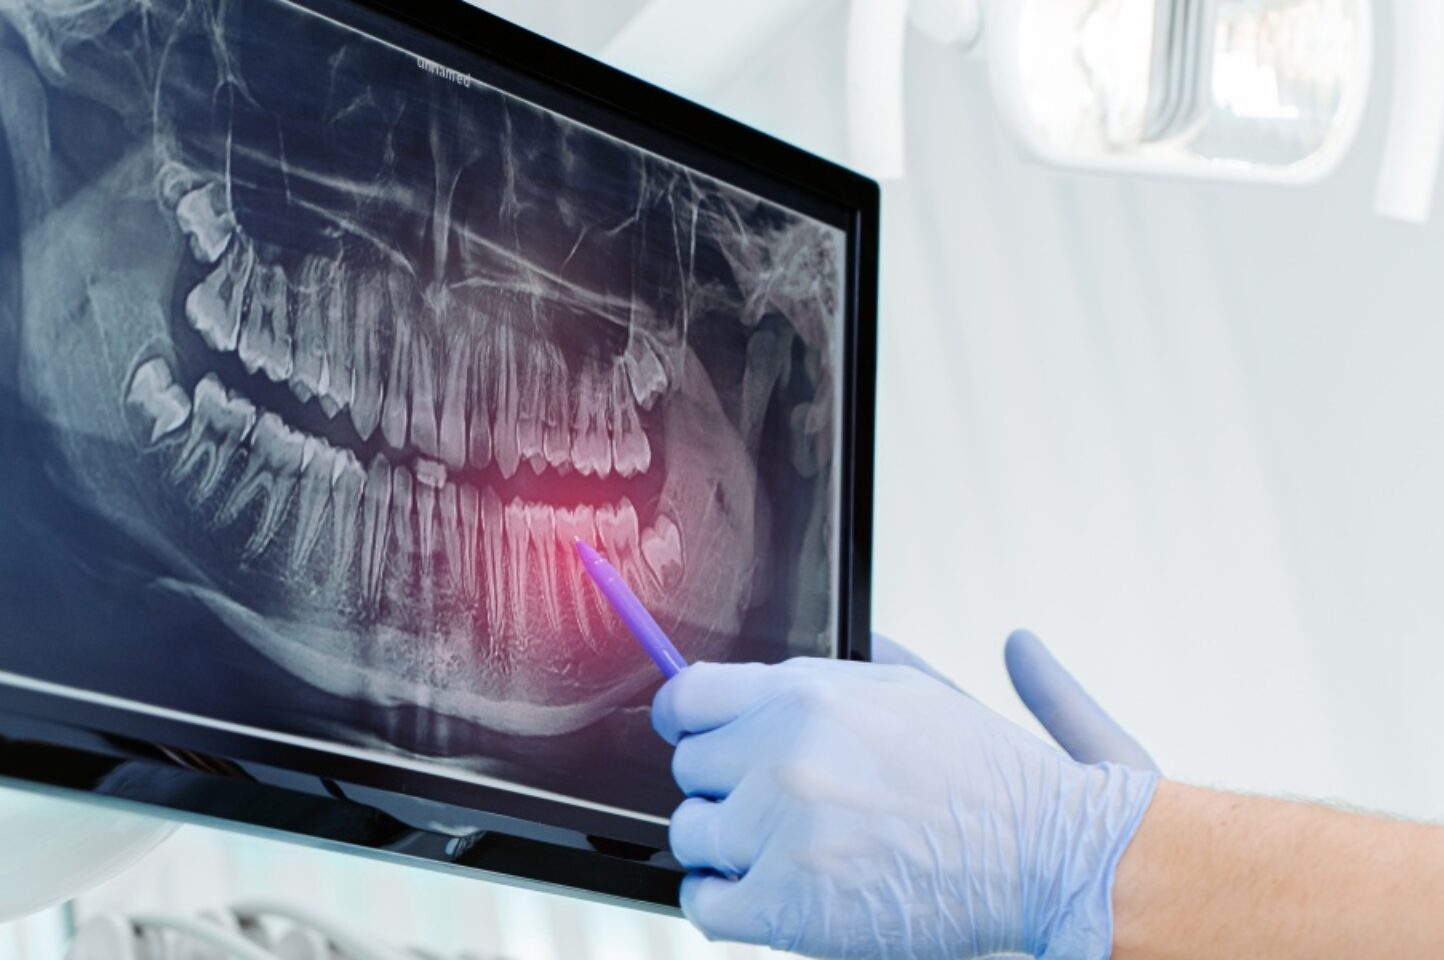

When it comes to caring for your teeth, some of the most important things we look for are the ones you can’t see in the mirror.

That’s where dental X-rays come in. These powerful diagnostic tools allow us to look beneath the surface of your smile—into your teeth, roots, bone, and jaw—to catch problems early and guide effective treatment.

Most people are familiar with traditional 2D X-rays, which give quick, low-radiation images ideal for spotting cavities and bone changes. But with advanced 3D CBCT scans, we get an incredibly detailed, three-dimensional view of your teeth, bone, nerves, and surrounding structures—helping us diagnose complex conditions and plan treatments with much greater precision.

While a visual exam can catch surface-level issues like cavities or gum inflammation, 2D dental X-rays reveal problems that are invisible to the naked eye. These flat images give us valuable insight into areas we can’t see during a regular check-up, such as:

• Decay between teeth or beneath existing fillings.

• Infections in the bone or tooth roots.

• Abscesses or cysts.

• Bone loss due to gum disease.

• Tooth development issues, especially in children.

• Impacted teeth (like wisdom teeth).

• Tumours or other abnormalities.

Without 2D X-rays, your dentist is essentially working blind, especially early on when many problems don’t cause pain or show visible symptoms. These images are a quick, safe, and essential part of catching dental issues early and keeping your smile healthy.